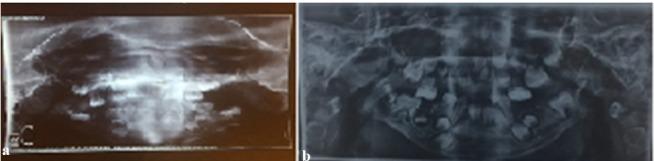

Goldenhar syndrome (GHS) is a complex syndrome characterized by relation of mandibular hypoplasia, abnormality of the ear, ocular dermoid and vertebral disorders and hemi facial macrosomia. Treatment protocol depends on the patient's age and systemic clinical presentations, with a multidisciplinary method often being required. This case report describes a typical 6-year-old female patient who presented to the Department of Pediatric Dentistry, Faculty of Dentistry, University of Medical Sciences, Kerman, Iran with mandibular hypoplasia, facial asymmetry, ear tags and ocular dermoid after plastic surgery. Diagnosis was based on clinical aspects, radiology and laboratory findings. GHS is a developmental complaint that can disturb many aspects of the patient's life; therefore, immediate treatment from birth is necessary.

戈尔登哈综合征(GHS)是一种复杂的综合征,其特征为下颌发育不全、耳部异常、眼皮样囊肿、脊柱疾病以及半侧颜面巨大症。治疗方案取决于患者的年龄和全身临床表现,通常需要多学科方法。本病例报告描述了一名典型的6岁女性患者,她因下颌发育不全、面部不对称、耳赘和眼皮样囊肿在接受整形手术后就诊于伊朗克尔曼医科大学牙科学院儿童牙科。诊断基于临床症状、放射学和实验室检查结果。戈尔登哈综合征是一种发育性疾病,会干扰患者生活的许多方面;因此,从出生起就需要立即进行治疗。